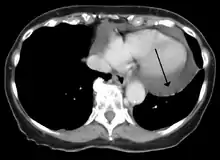

Cardiac CT and MRI scans: cross-sectional imaging with computed tomography (CT) can help localize and quantify the effusion, especially in a loculated effusion (a effusion contained to one area).[10] CT imaging also helps assess for pericardial pathology (pericardial thickening, constrictive pericarditis, malignancy-associated pericarditis).[1] Whereas cardiac MRI is reserved for patients with poor echocardiogram findings and for assessing pericardial inflammation, especially for patients with continued inflammation despite treatment.[4] CT and MRI imaging can also be used for continued follow up on patients.